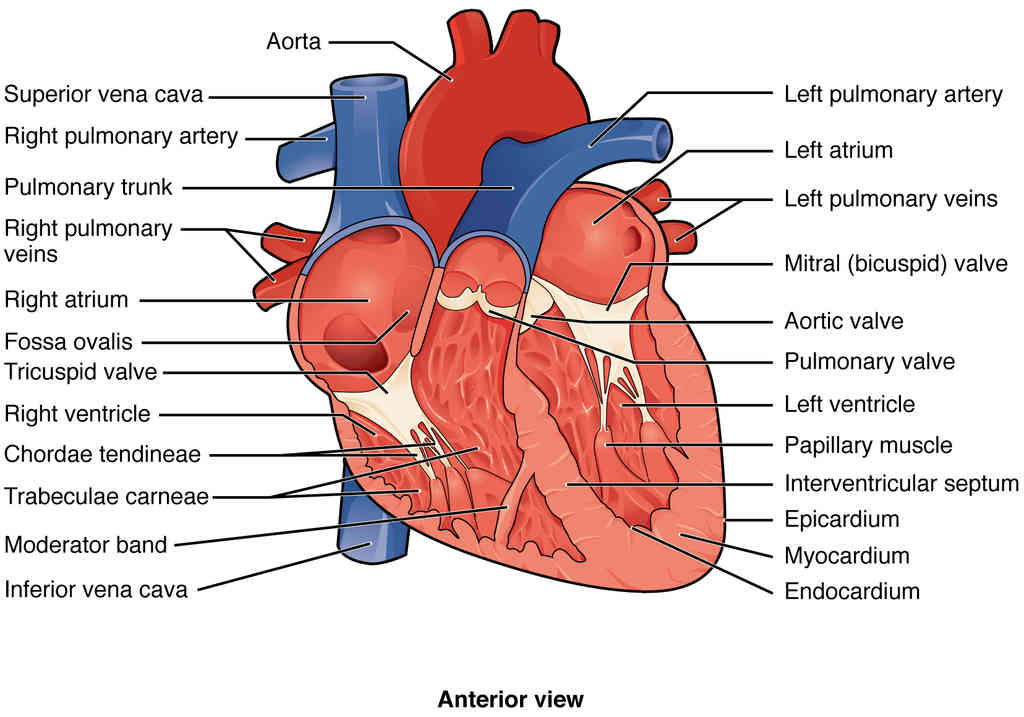

This page is under construction. For now, it is just a resource of the images found in the OpenStax Anatomy and Physiology Handbook. It wil slowly change into a revision tool. Each slide has a number. Use this to refer to the slide. When completed, it will have an unlabelled section, with labelled slides in parallel. On the unlabelled slides, write your answer and use the labelled slide to assess yourself. Keep track by also noting the number on each slide. Improvement at each attempt is important, more so than full marks on a first attempt.